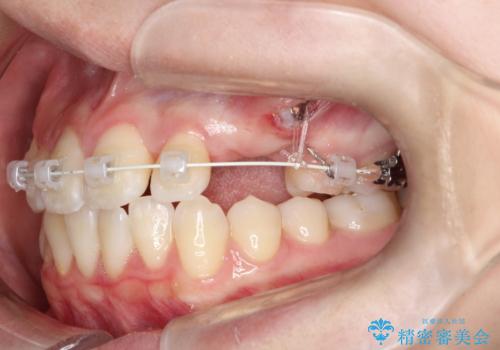

- 左上の八重歯を気にされて来院されました。精密な検査の結果、歯列全体を広げながら八重歯を奥へ移動させることで、美しい歯並びと機能的な咬み合わせが得られると診断。患者様のご希望に合わせ、透明で目立ちにくい**インビザライン(マウスピース矯正)**による治療計画を立案しました。抜歯を避け、歯を少しずつ遠心(奥)へ移動させることで、歯が並ぶスペースを確保し、叢生(歯のデコボコ)を改善します。

今回の矯正治療では、透明なマウスピース型の装置インビザラインを使用しました。この装置は目立ちにくく、取り外しが可能なため、食事や歯磨きも普段通りに行えます。遠心移動という方法で奥歯を後方に動かし、前歯を並べるためのスペースを確保。これにより、抜歯することなく、左上の八重歯を含む叢生を効果的に改善し、整った美しい歯並びと良好な咬み合わせを獲得していただけました。